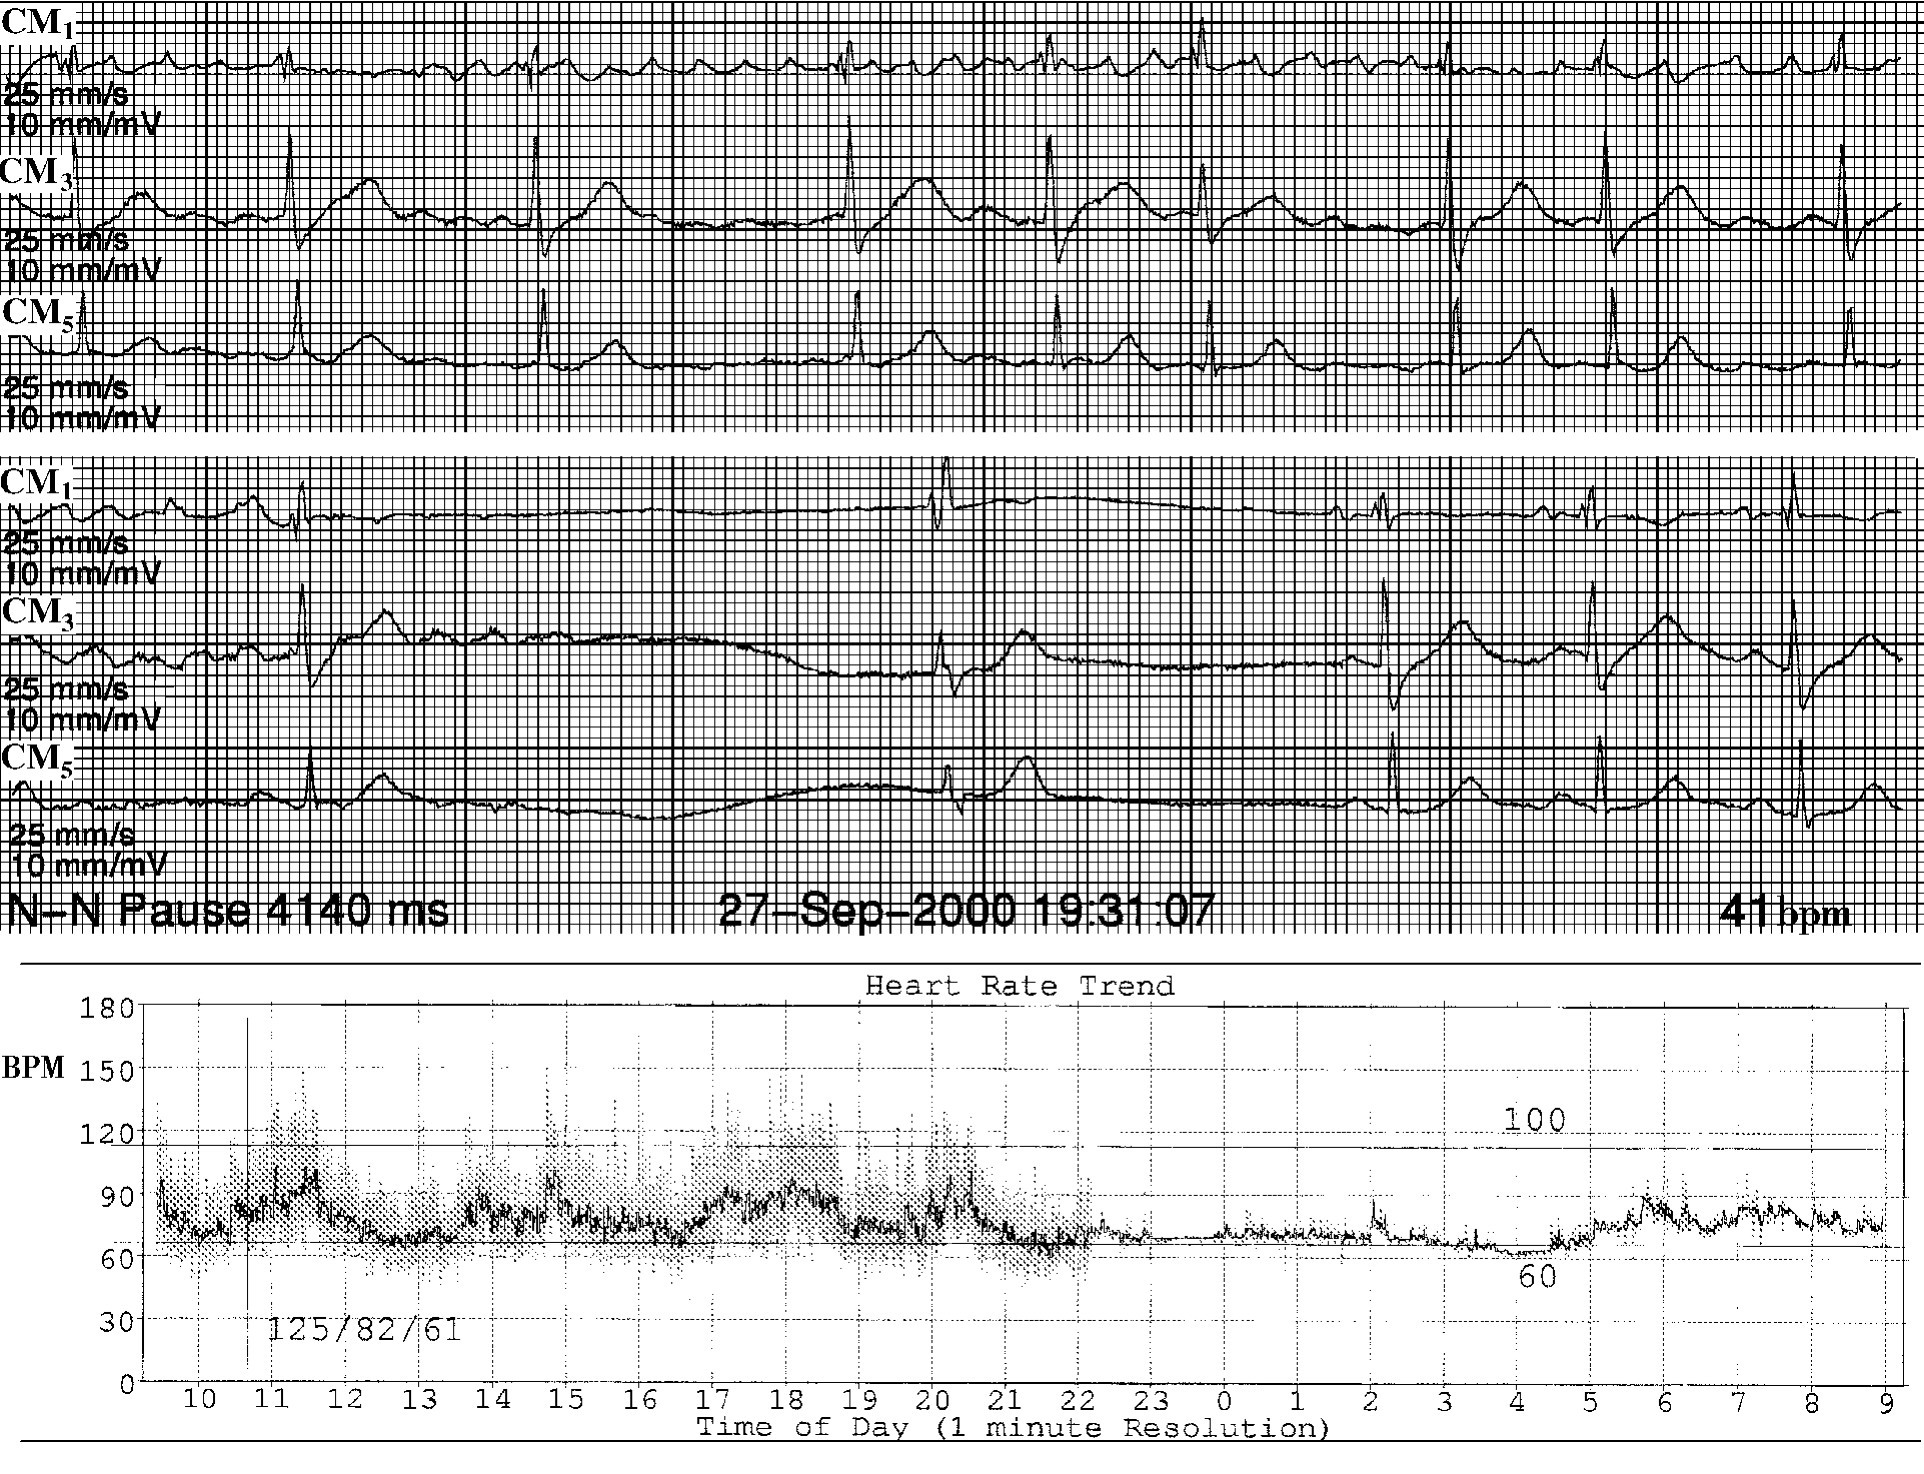

3.逸搏—夺获二联律 房室交界性逸搏的异位激动沿结间束向上逆传至窦房交界区内,并隐匿性传到窦房结,使之发生节律重整,促使窦房结自律性增高,频率加速,节律提前,而发生心室夺获(图43-9)。由于异位激动由结间束向上逆传,未经心房肌,故看不到逆行P波。

4.插入性房性期前收缩产生次等周期代偿间期 插入性房性期前收缩在窦房交界区产生隐匿性传导,使下一次窦性激动产生干扰性窦性传出延缓,而产生次等周期代偿间期(界于无代偿间期与等周期代偿间期之间)(图43-10)。

img755

图43-9 交界性逸搏伴窦性夺获二联律

img756

图43-10 插入性房性期前收缩产生逆行性窦房交界区内隐匿性传导

第8个QRS波群为插入性房性期前收缩伴室内差异性传导,箭头所指为异性房性P',房性P夹于两个窦性P波之间,其P-P间期比窦性P-P间期稍长,形成次等代偿间期。由于插入性房性期前收缩逆行窦房交界区,产生了隐匿性传导,其后的激动下传恰遇新的不应期,故产生了干扰性传出延缓,期前收缩后的第1个窦性P波后延,造成次等周期代偿间期